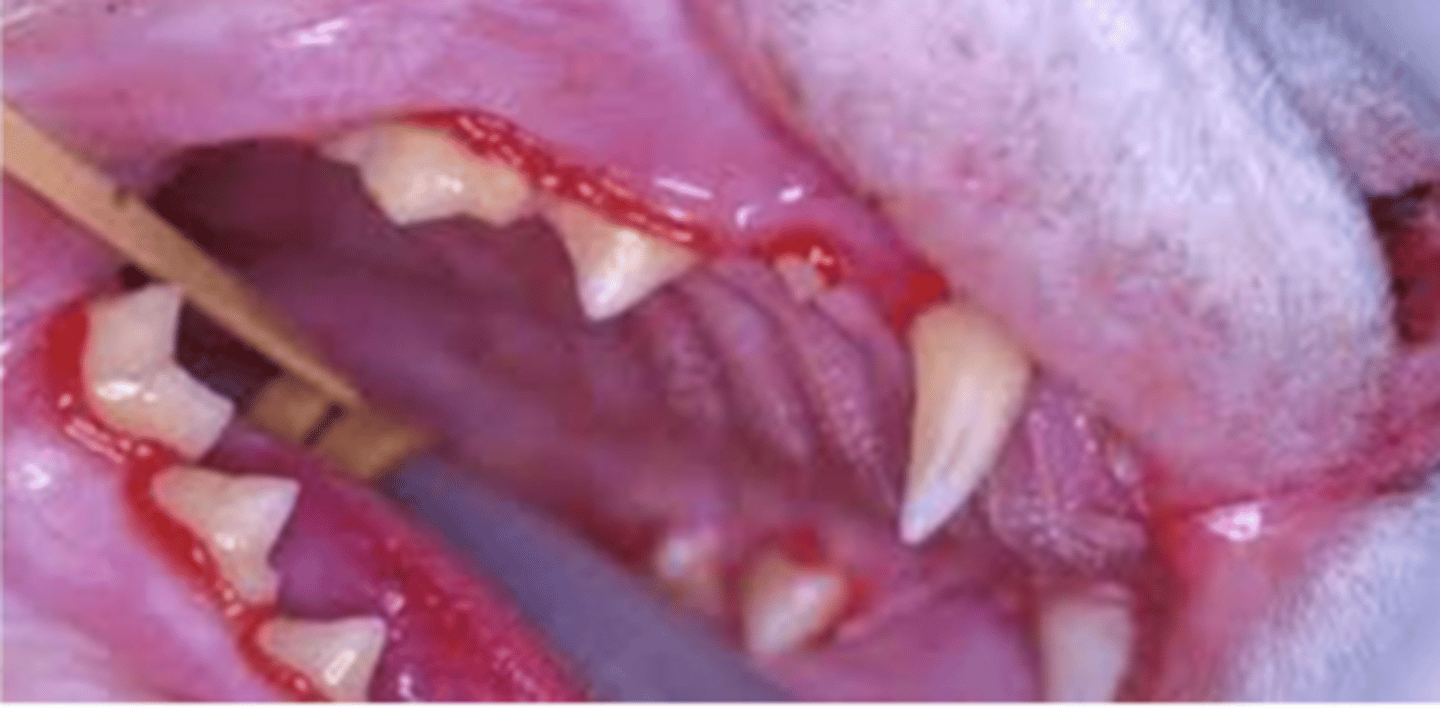

gingivitis; viral infection

what is the medical term for the condition of this cat? what is likely the etiology?

we see the most cases of stomatitis in what species?

stomatitis

what does this cat have?

stomatitis

this cat has what condition?